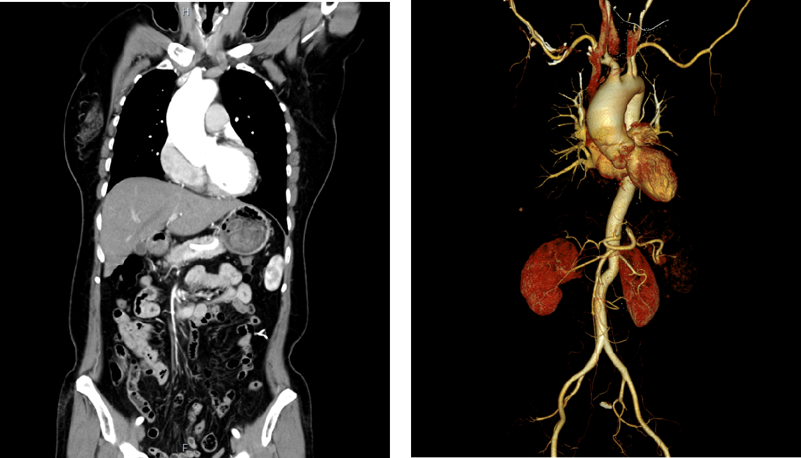

此次接受手术的韩女士今年 53 岁,因头晕不适在当地医院就诊,心脏超声检查提示其主动脉瓣中重度反流、升主动脉瘤样扩张,头颅 MRI 还显示存在颞叶微出血灶/小海绵状血管瘤。当地医院建议行主动脉瓣置换手术,但该方案存在明显弊端:置换机械瓣膜需终生抗凝,可能加重颅内血管瘤破裂出血风险;置换生物瓣膜则面临远期衰败的寿命问题,这让韩女士和家属陷入两难。

接诊后,院心胸外科主任吴奇勇带领团队经综合评估认为,主动脉瓣成形联合升主动脉置换手术是适配患者的个体化最优方案。该方案可修复并保留患者自身主动脉瓣膜,术后仅需短期抗凝,既规避了长期抗凝引发的颅内出血风险,也无需担忧生物瓣膜远期衰败问题。

手术过程中,团队精细探查评估患者主动脉瓣情况,对瓣膜融合、增厚部位进行精准切削,对脱垂部位实施精细修复,成功恢复主动脉瓣严密的闭合功能,随后以人工血管替换了扩张的升主动脉。心脏复跳后,术中即刻食道超声检查显示,患者主动脉瓣未见明显反流,瓣膜成形效果理想,手术全程顺利。

据吴奇勇主任介绍,常州二院心胸外科已在阳湖、延陵两大院区成功开展多例主动脉瓣成形手术,均取得良好疗效。临床中,主动脉瓣关闭不全患者常合并升主动脉瘤样扩张,传统手术多采用主动脉瓣置换联合升主动脉置换方案,而主动脉瓣成形联合升主动脉置换成为此类患者的新选择。